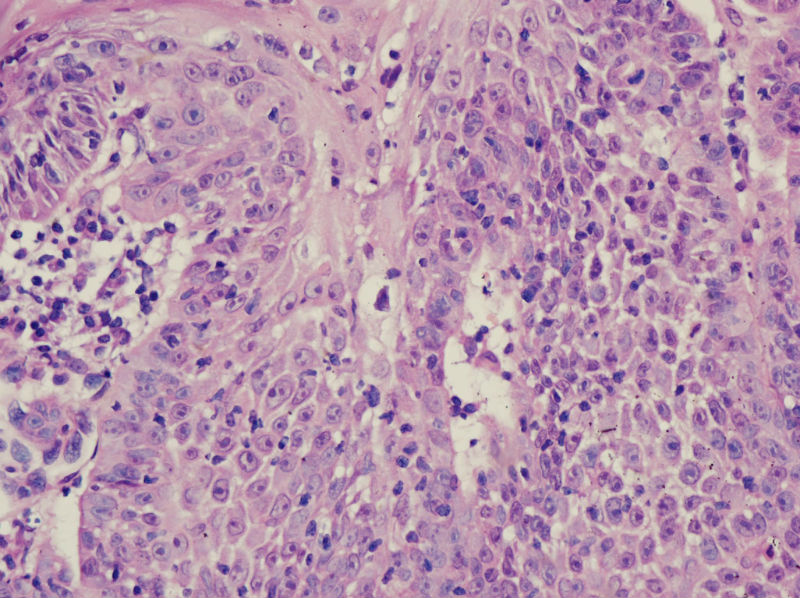

男,45岁,上唇菜花样肿物,请老师指教

图4

高分化鳞癌

倾向于鳞癌,恶黑不除外。